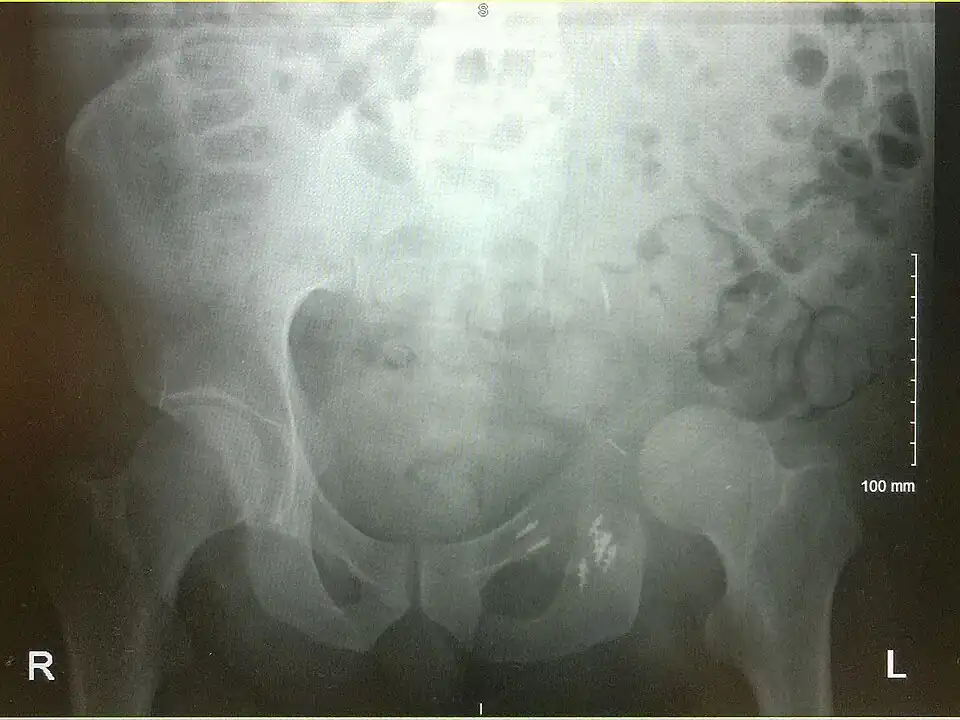

An x-ray of a limb-sparing hemipelvectomy on the left side of a male pelvis taken one month after surgery. -

An x-ray of the same pelvis taken eighteen months after surgery highlighting the femur migration to its final resting place.